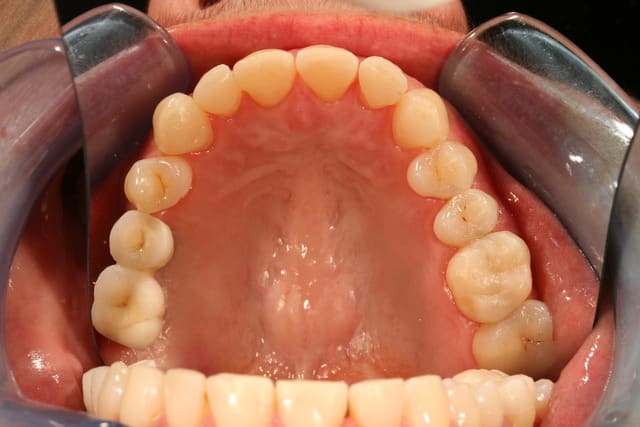

Occlusal jyrk8g - Eugenol